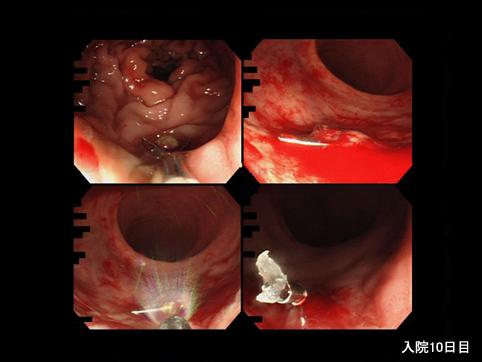

A case of acute hemorrhagic rectal ulcer that was found in an elderly bedridden patient.

Fukuoka Pref., KYUSHU UNIVERSITY HOSPITAL (Dr.Masunari)

Sex

male

Age

70-74

Inflammatory or ulcerative disease / lesions/Others

Large intestine(Colon)/Rectum

Endoscopy

25 - 29